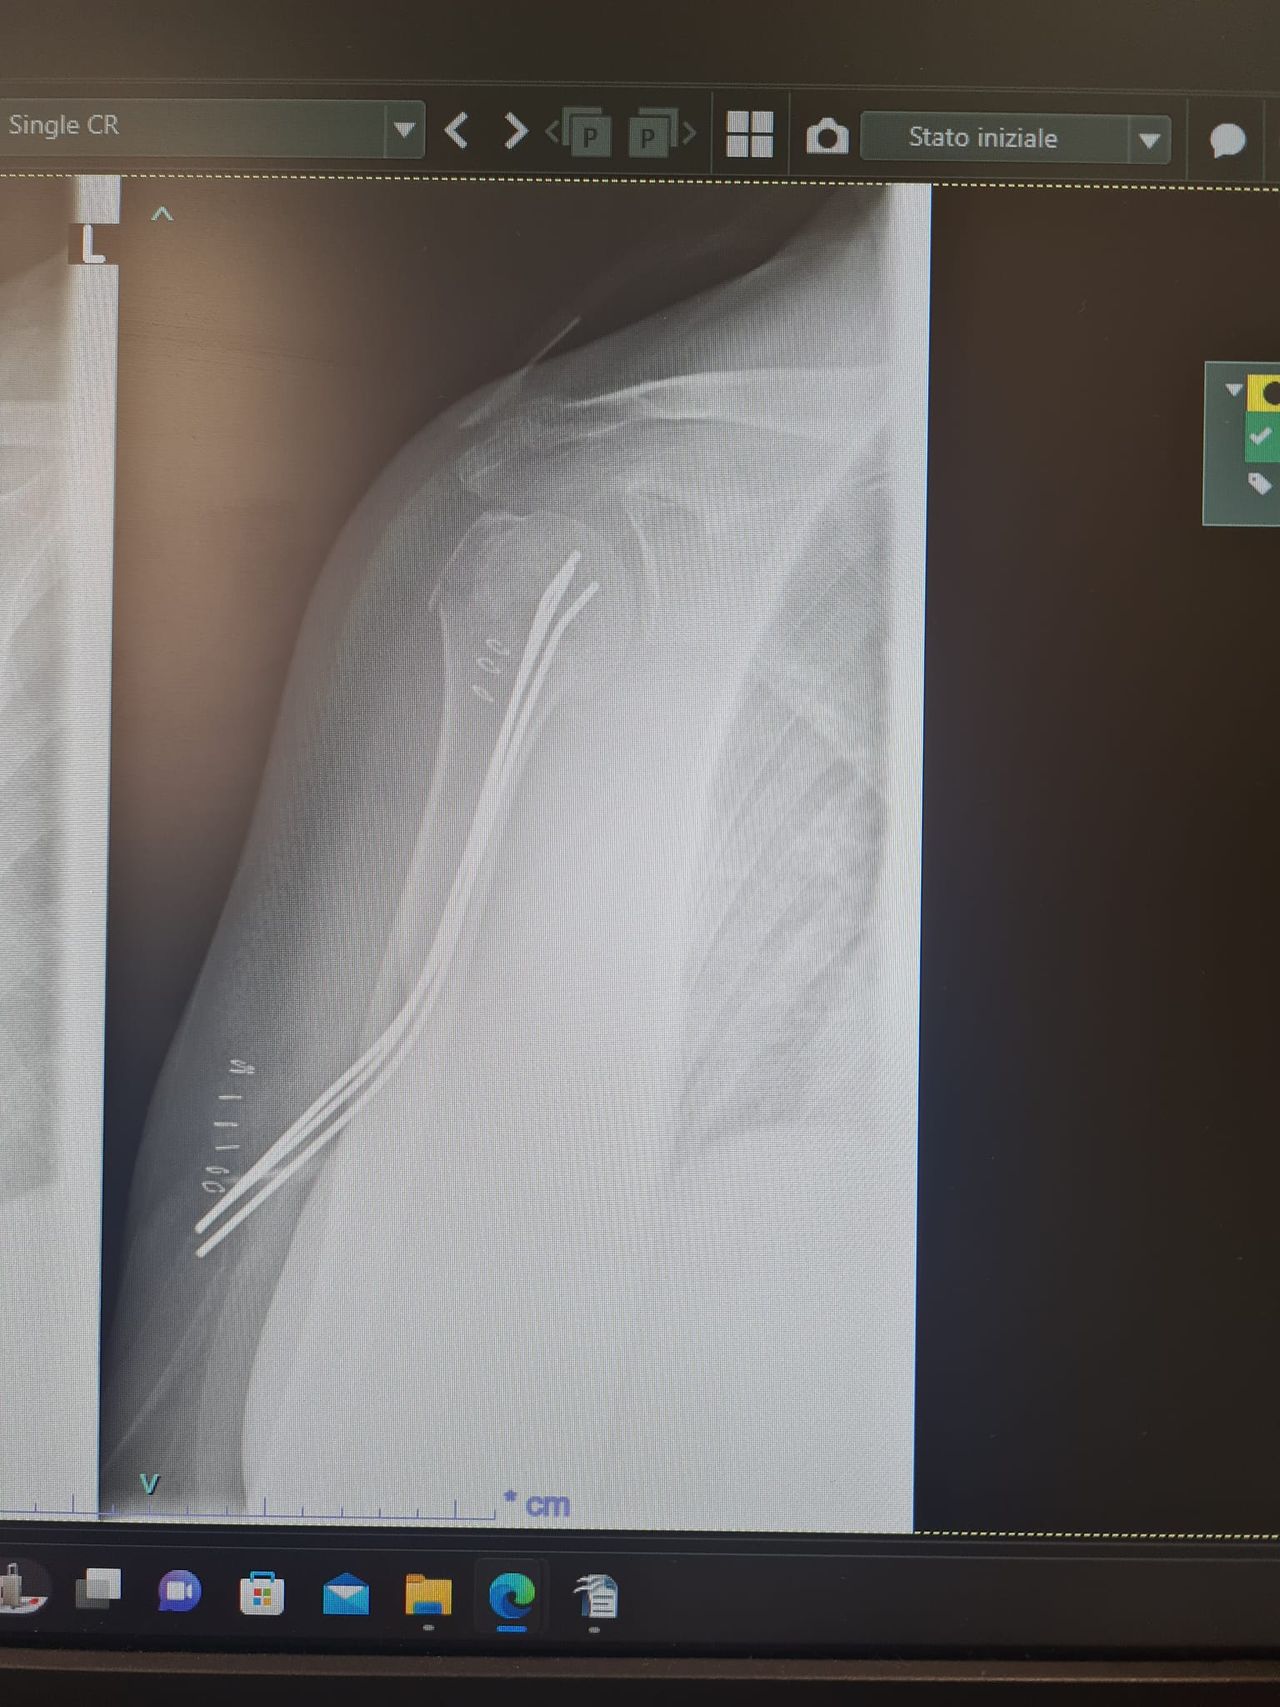

Unico chirurgo ortopedico nel centro-sud Italia ad effettuare intervento di osteosintesi per le fratture dell'omero prossimale con tecnica mini-invasiva di Kapandji da me modificata.